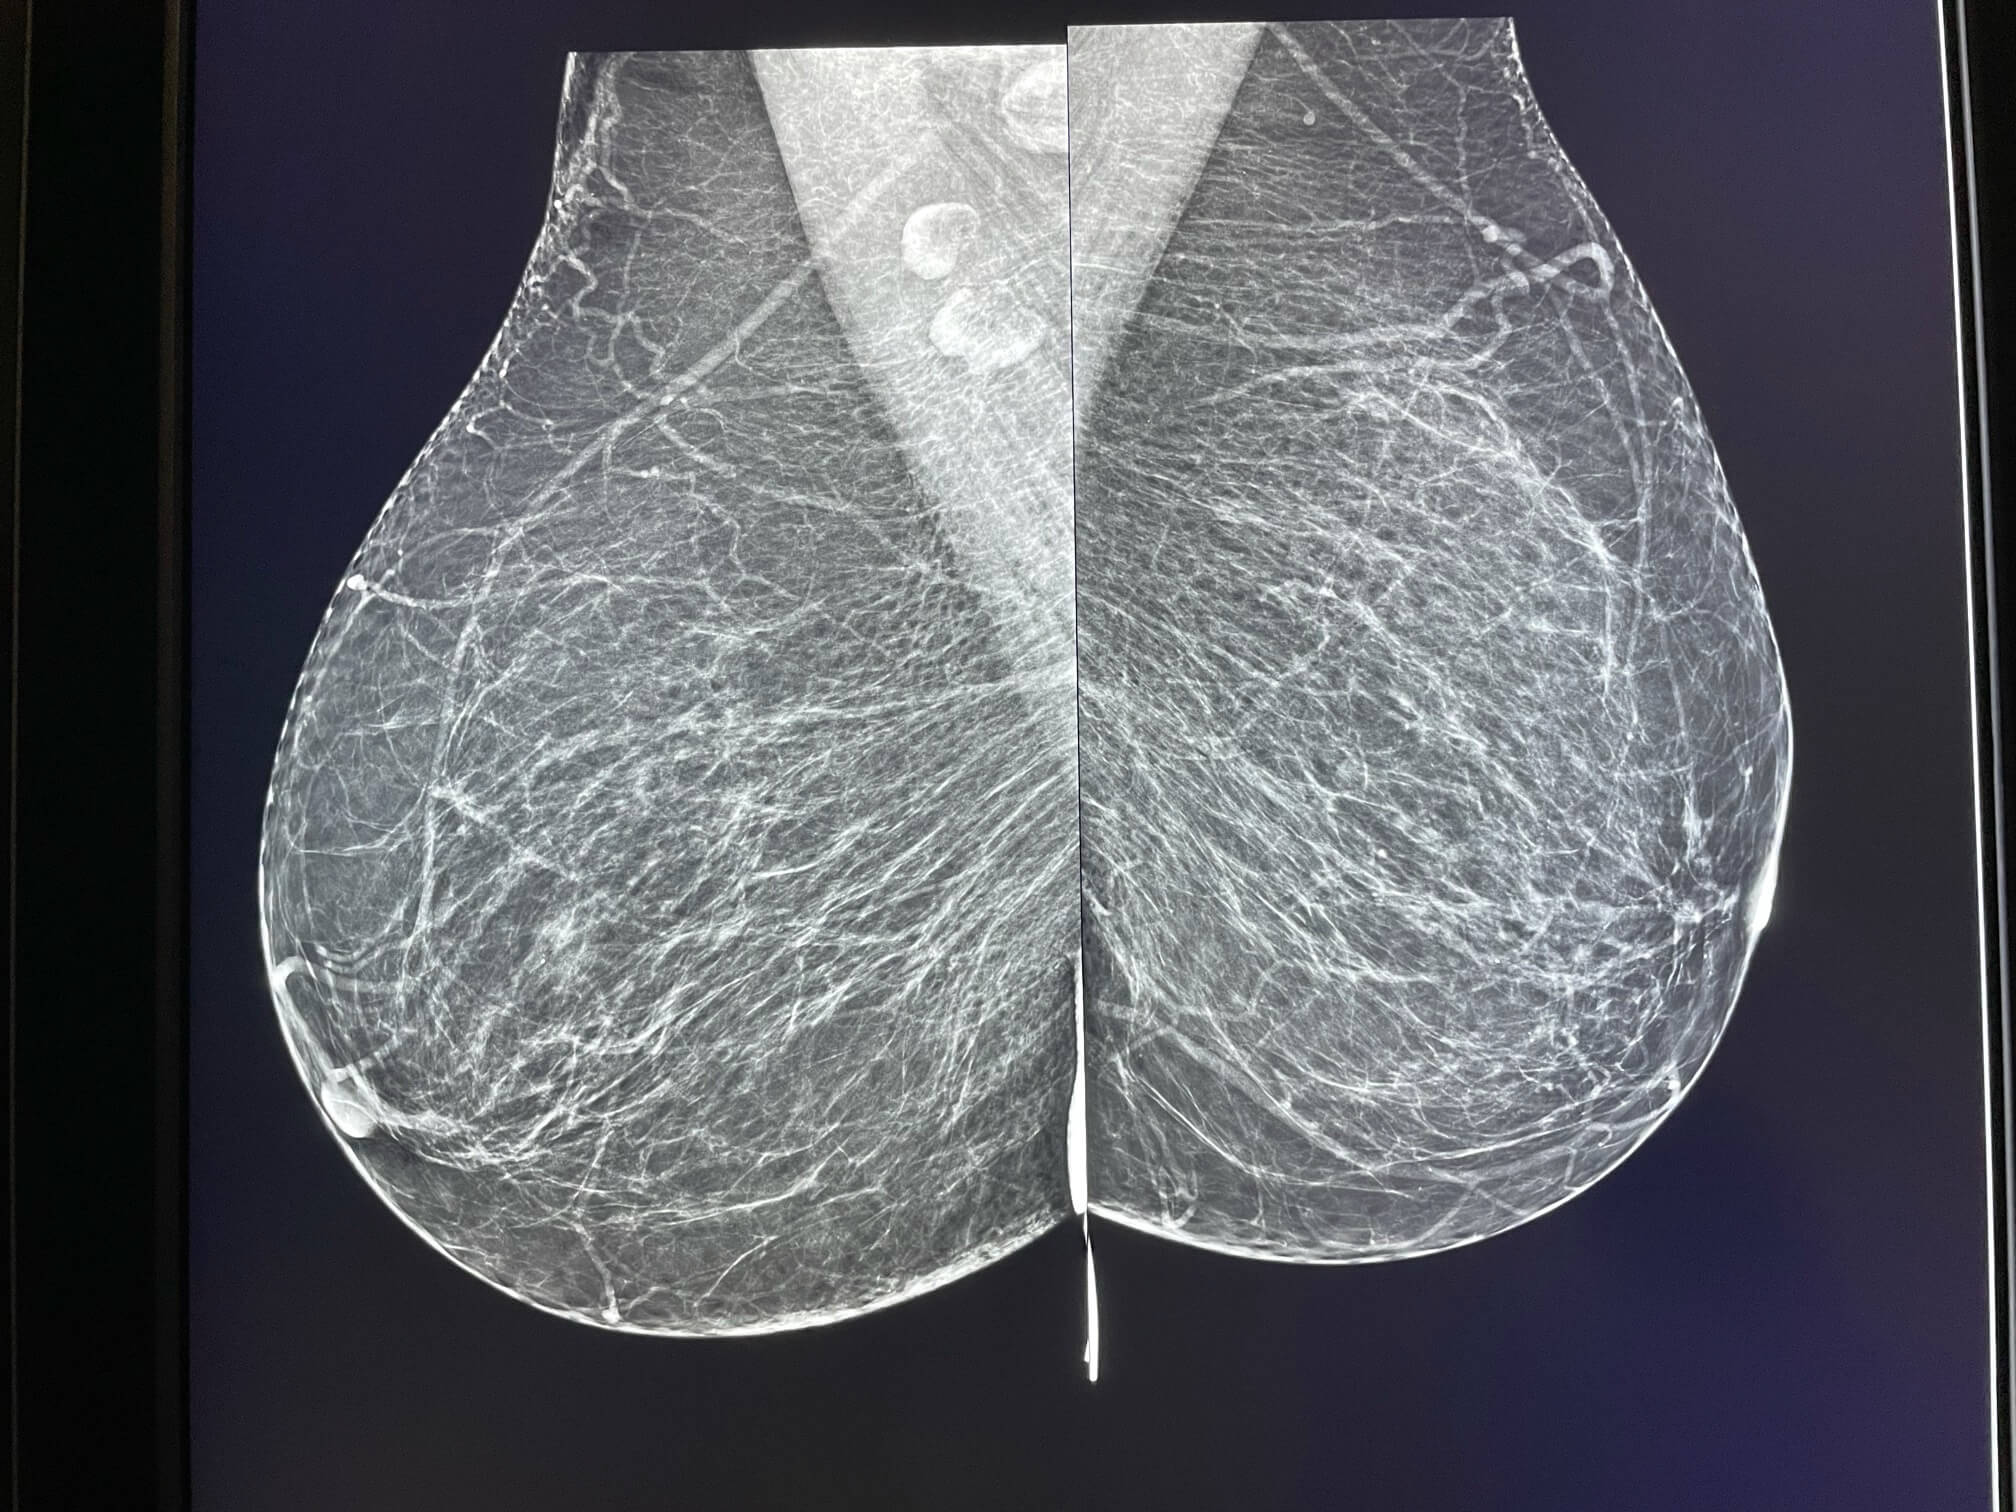

Patiente de 67 ans, mammographie de dépistage.

La mammographie met en évidence un surcroît d’opacité rétro-mamelonnaire d’aspect inchangé par rapport à l’examen de 2018, considéré à l’époque comme un reliquat fibro glandulaire banal.

MammoScreen™ pointe cette anomalie avec un drapeau orange.